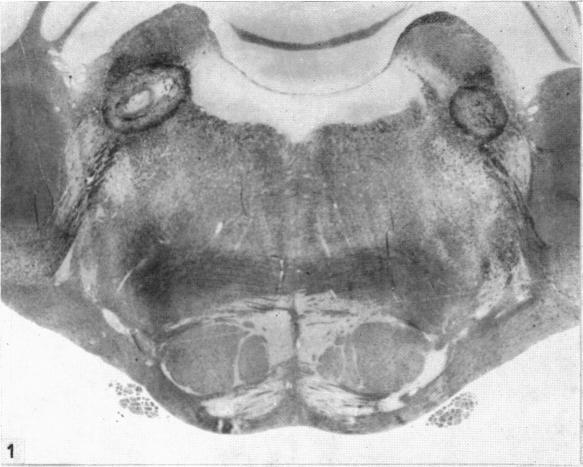

The dorsal trigeminal tract in the rhesus monkey.

J Anat. 1957 Jan;91(1):82-90.